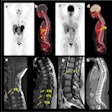

In the prospective study, raw data were reconstructed to virtual monoenergetic images at 50 keV using filtered back-projection (FBP) -- the standard CT image reconstruction method for several years; adaptive statistical iterative reconstruction-V algorithm at 50% blending (AV-50); and deep learning-based reconstruction at low, medium, and high strength.

The investigators found that deep learning-based image reconstruction reduced image noise compared to AV-50 while better preserving the average noise power spectrum (NPS) frequency. Deep learning-based image reconstruction maintained CT number values and improved the signal-to-noise ratio (SNR) and contrast-to-noise ratio (CNR) compared with AV-50.

The scientists also indicated that deep learning-based reconstruction is superior to AV-50 in noise reduction, with fewer shifts of the average spatial frequency of NPS toward low frequency, and larger improvements of NPS noise, noise peak, SNR, and CNR values.